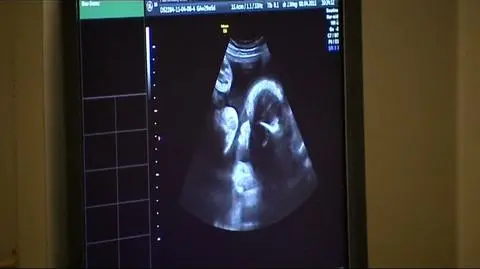

Tym, dla których ostatnią szansą jest in vitro - rząd finansowo już nie pomoże. Refundację tej metody ma zastąpić Narodowy Program Prokreacji. Niewiele jeszcze o nim wiadomo - poza tym, że ma promować edukację i diagnostykę, czyli tzw. naprotechnologię. I choć medycyna nie uznaje tej metody za leczenie niepłodności - to są oczywiście pary, którym wnikliwa diagnostyka może pomóc - choć taką diagnostykę stosuje się też przed in vitro. Medycznie nie jest to więc alternatywa dla in vitro, ale niekiedy jest równie kosztowna.